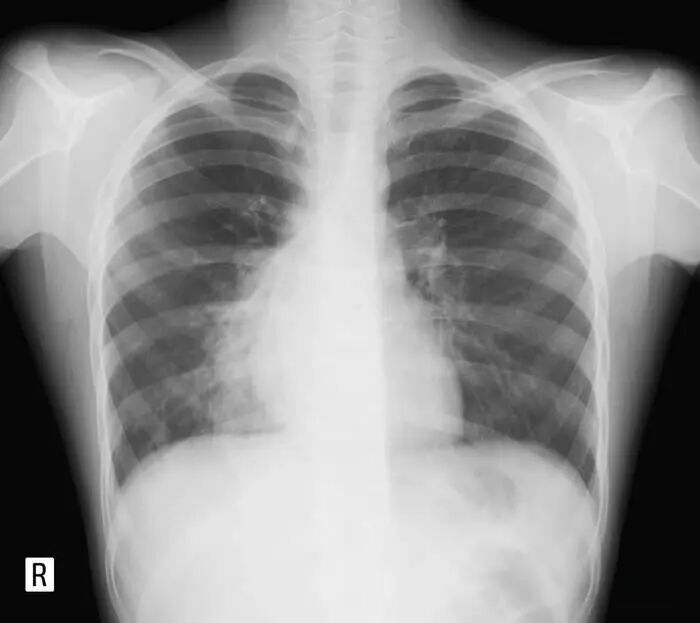

带去拍胸片,结果还是说支气管炎,还说如果是上面的血可能是鼻血,如果是下面的血可能是肺结核之类的。最后刷到我之前写的文章,咳嗽可能是因为鼻炎鼻涕倒流引起的。

咳嗽拍胸片的问题,很多医师根据胸片的诊断来治疗,就会和上文一样,按支气管炎的方向来治,没找到病因怎么可能治好。